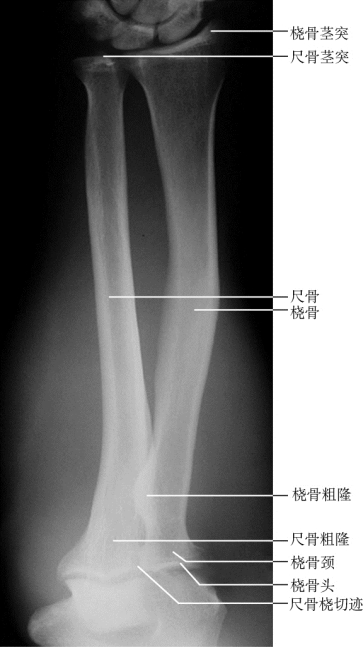

学习“资料”中《下肢骨及其连接》,掌握下肢骨的组成、连接、位置、骨性标志,下肢关节的特点及运动,熟悉下肢骨及其关节的影像解剖学特点。